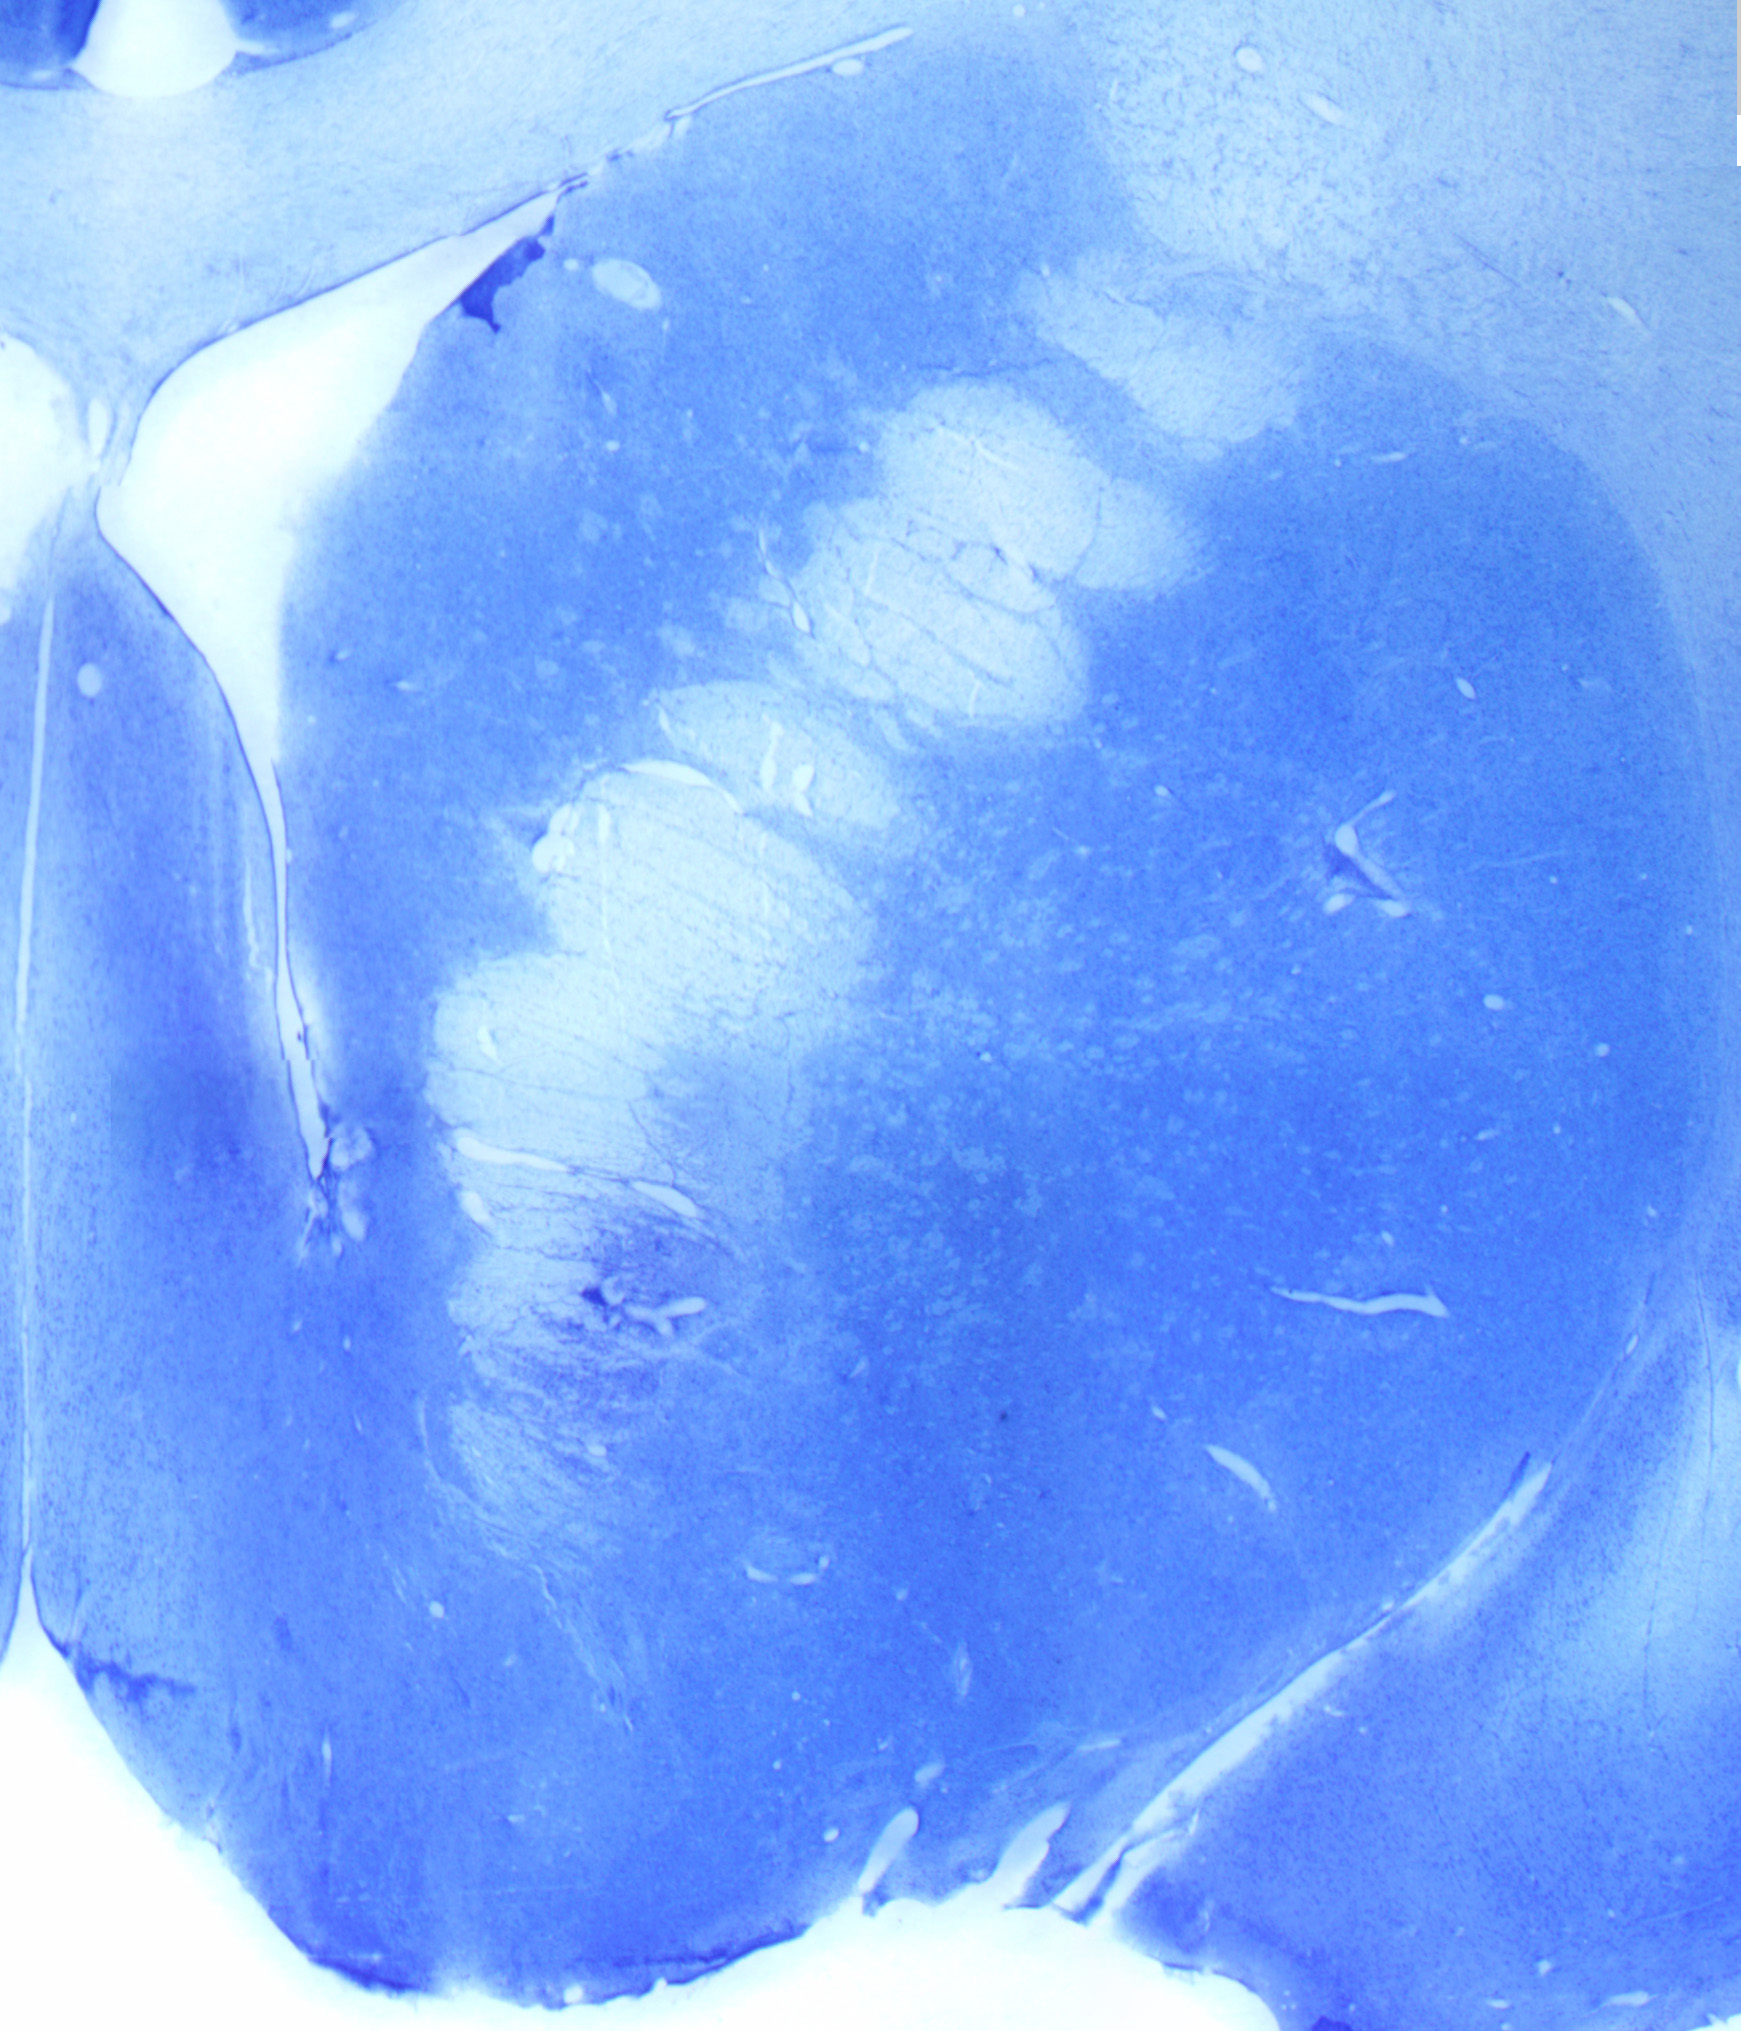

Spock_markinglesion1